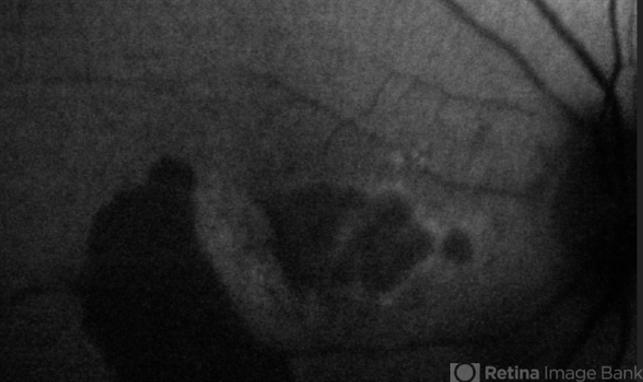

- RPE Tear

- Condition/keywords

- retinal pigment epithelium (RPE) tear, wet age-related macular degeneration (wet AMD), choroidal neovascular membrane (CNVM)

- Scanning laser ophthalmoscope

- Autofluorescence image: Note the discrete hypo-autofluorescence due to the absent RPE temporally. Note also the hypo-autofluorescence due to geographic atrophy centrally.